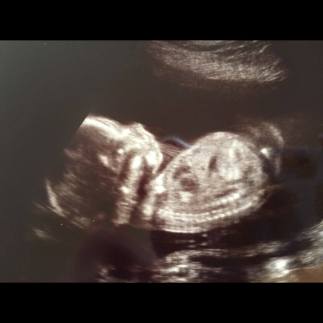

304676_4607409346704_1318046805_nFor those who have been readers for a few years, you know that I spent time discerning the religious life before I married my husband.  For those who have not been reading as long, here’s the short of it: after completing my first year of grad school, I felt called to discern the religious life.  I spent eight months in formation before making the decision to leave the convent and pursue a different vocation.  I spent a year working and living with my family in New Jersey before I returned to Washington, DC to finish my degree.  By the time I graduated that spring, I was just two weeks from getting married, four weeks from learning that my husband and I were expecting our first child.  It was a whirlwind of a ride, and probably the most roundabout way of discovering my vocation to marriage.

14212739_10210677383634195_7577653981281141155_nAnd two years later, here I am: a wife and mother.  I have finally found my vocation, and I am no longer running.  I am happy where I am.  I am happy with the life that I have chosen, the life that has chosen me.  Now I am doing a different kind of running, the running that is required of any mother chasing after a child who is growing up too fast for her.